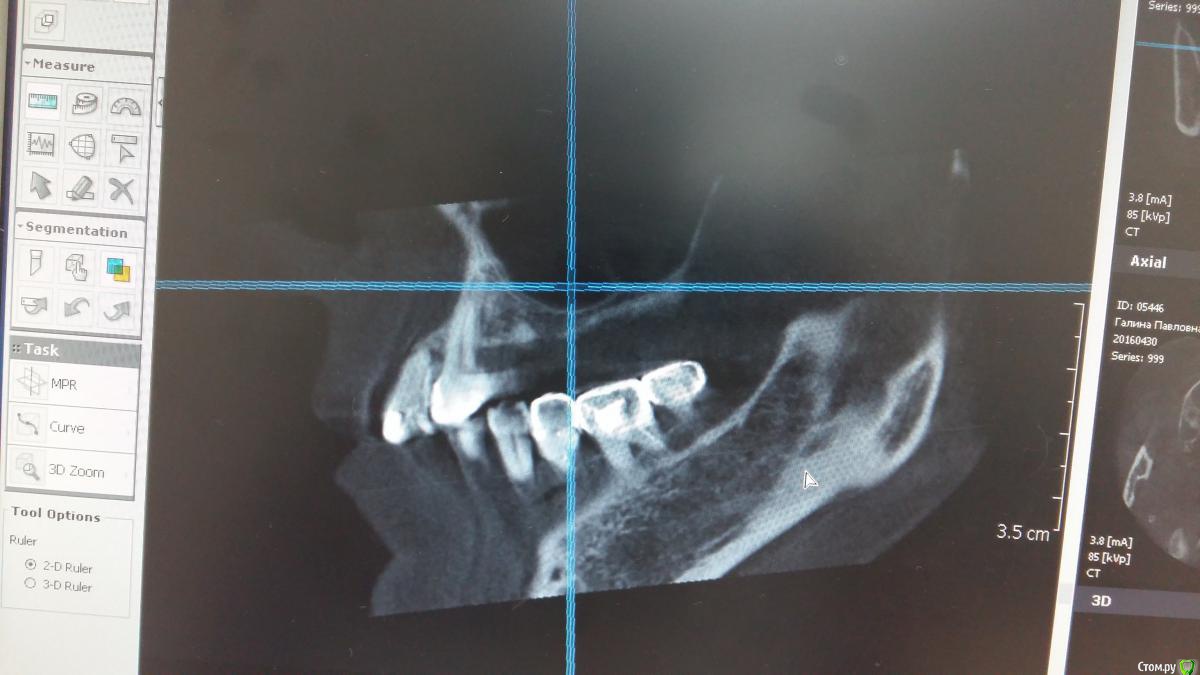

Zubnik7 Опубликовано 30 сентября, 2016 Поделиться Опубликовано 30 сентября, 2016 Подскажите варианты проведения синус лифтинга,корень удален 1 Ссылка на комментарий

Доктор Добрых Дел Опубликовано 30 сентября, 2016 Поделиться Опубликовано 30 сентября, 2016 Одно большое окно, отслойка в обеих камерах, удаление перегородки (части перегородки), отслойка дальше сколько нужно, графт мембраны и т.д. А вообще срезы бы по подробнее - не до конца понятна локализация септы 1 Ссылка на комментарий

Nazim_NV86 Опубликовано 30 сентября, 2016 Поделиться Опубликовано 30 сентября, 2016 Это неполная перегородка. Сделайте овальное окно горизонтально. При отслоении будьте осторожны. С самой перегородки десна будет отслаиваться неохотно. Не порвите. Дальше всё как обычно. Если надорвали, то 2 слоя мембраны на перфу. Ссылка на комментарий

Zubnik7 Опубликовано 30 сентября, 2016 Автор Поделиться Опубликовано 30 сентября, 2016 Перегородка не полная,сейчас выложу новые срезы,более информативные Ссылка на комментарий

Zubnik7 Опубликовано 30 сентября, 2016 Автор Поделиться Опубликовано 30 сентября, 2016 Новые срезы Ссылка на комментарий